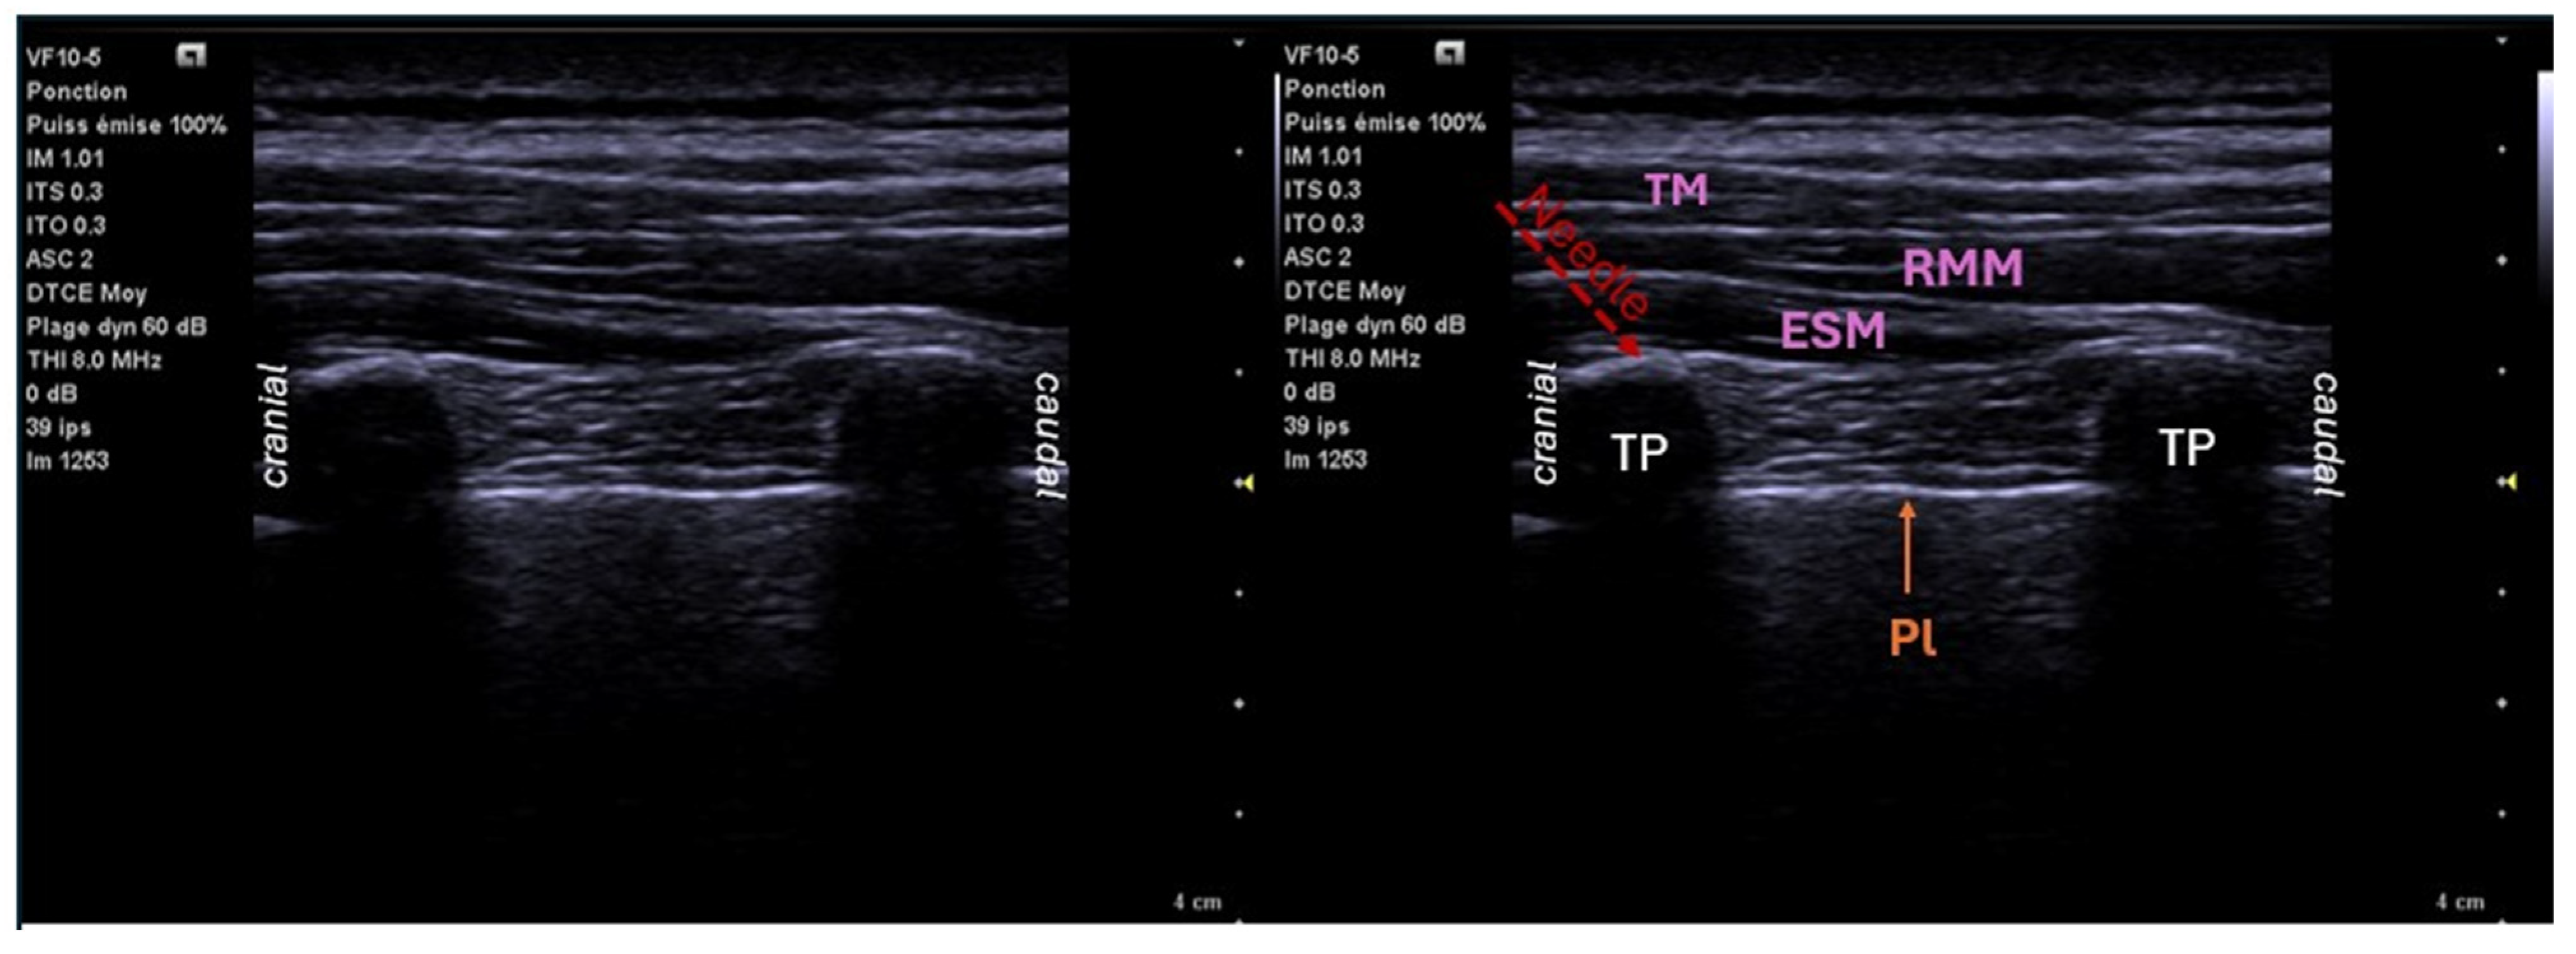

6.1. Paravertebral Block (PVB)